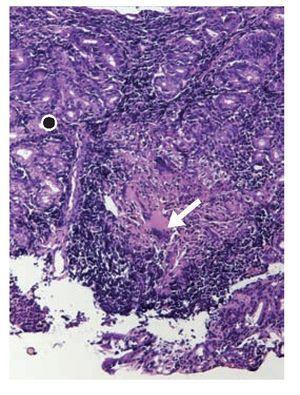

Figura 4. Fotomicrografía de luz de biopsia de mucosa gástrica (punto negro) en la que se observa un infiltrado inflamatorio de carácter granulomatoso con necrosis caseosa y células gigantes multinucleadas (flecha).